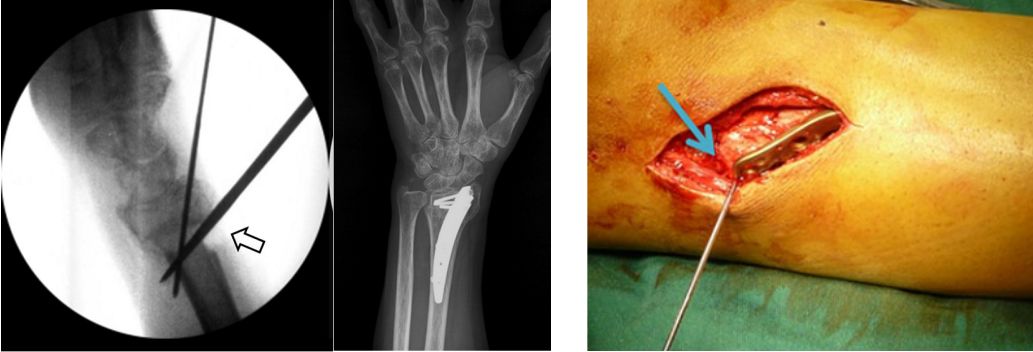

2008年来自美国的学者Ruland在J Hand Surg上报道了应用克氏针制成的动态外固定支架治疗不稳定型近节指间关节骨折脱位和pilon性损伤。

2014年Tech Hand Surg报道了日本学者Mohamed Adi将Iselin技术进行改良,闭合复位骨折,经皮穿针并将克氏针在外部锁定,用来治疗Bennett骨折。

21、克氏针交锁固定

术中透视骨折复位克氏针固定后,将其中一枚克氏针折向另一枚克氏针,并绕着第二枚克氏针返回来,此时第二枚克氏针绕第一枚克氏针返折缠绕,形成相互交锁。